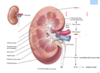

Quelles sont les deux faces du reins?

- convexe, externe

- concave, interne fait face à la colonne vertébrale (fente verticale ou hile au niveau duquel: uretère, nerfs issus du SNS*, artère et veine rénales, ainsi que vaisseaux lymphatiques)

Quelles sont les 3 zones du rein?

- externe (cortex rénal)

- intermédiaire (médullaire rénal ou médulla)

- interne (bassinet)

Que comprend la zone intermédiaire du rein et sa fonction?

- comprend tout les pyramide rénal (trait)

- chargé de retenir l’urine par la terminaire des pyramide (les papille rénal)

Que comprend la zone interne du rein et sa fonction?

interne (bassinet) retient l’urine avant de se déverser dans uretere, calice mineur sont à la terminaison des papile rénal et tous les calice mineur se réunisse pour former le calice majeur